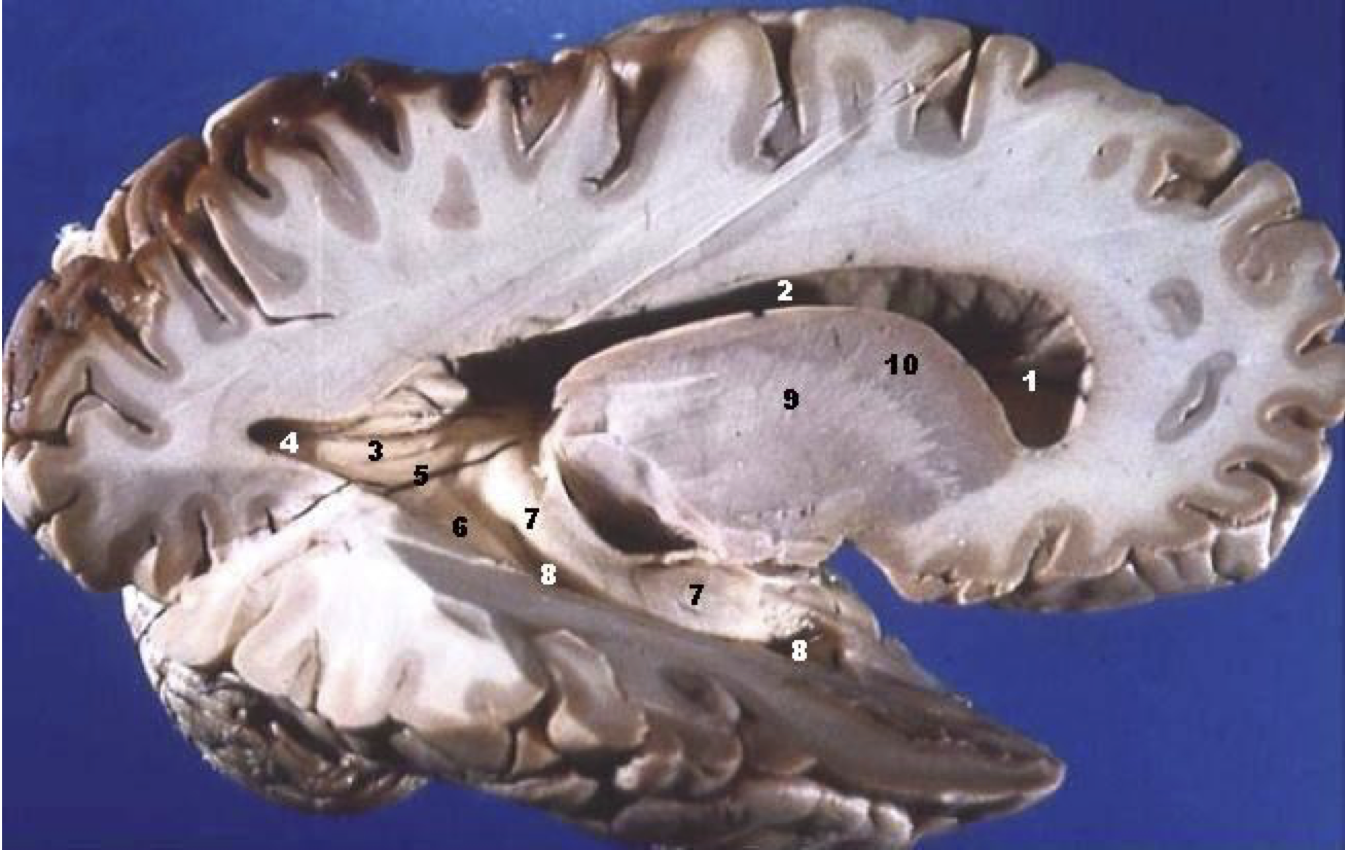

Basser (1994), Basser and Pierpaoli (1996)